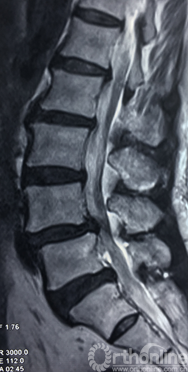

术前腰椎核磁共振矢状面